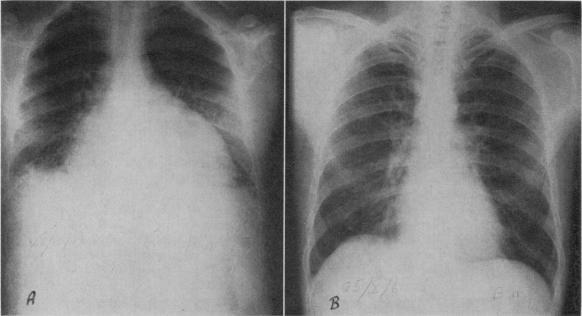

Quebec beer-drinkers' cardiomyopathy: radiological aspects.

Can Med Assoc J. 1967 Oct 7;97(15):905-9.